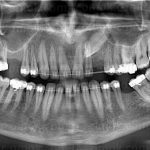

Tedavi Yöntemleri Self-Ligating Sistemler Gölcük Ortodonti Lingual Ortodonti Fonksiyonel Aparey eCligner Sistemi Ağız Dışı Apareyler Hareketli Apareyler Gömülü Kanin Dişi Tedavisi